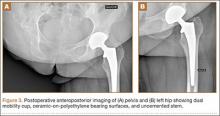

The patient was mobilized the day after surgery and permitted full weight-bearing. Recovery was uneventful, and the patient returned to work within 6 weeks of surgery after her scheduled appointment and radiographic examination (Figure 3). Ongoing regular clinical and radiologic surveillance are planned.